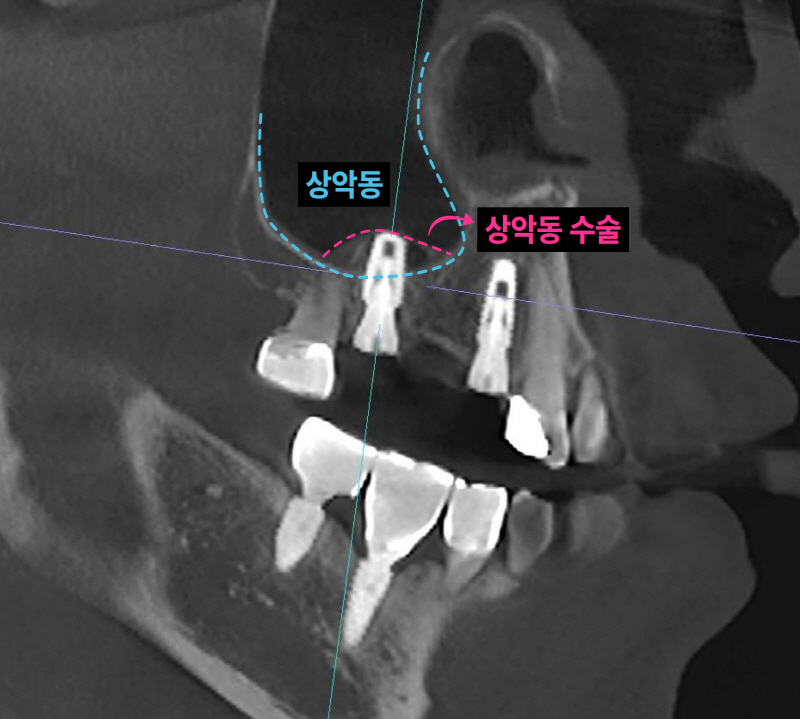

이미 신경치료된 치아 뿌리 끝에 염증이 잡혀있고 브릿지 아래로 2차충치가 크게 생겨서 임플란트로 치료 계획을 정했습니다. 임플란트 2개를 심고 치아 머리(크라운) 3개를 만듭니다. 여러 개의 임플란트를 심을 때 꼭 개수대로 임플란트를 심을 필요는 없습니다. 과거에는 발치, 상악동 수술, 임플란트를 전부 기다리며 나눠서 진행했는데 시간이 너무 오래 걸립니다. 저는 최대한 치아가 없는 기간을 단축시키기 위해서 치아를 뽑고(발치) 동시에 임플란트를 심으며 뼈가 없는 경우 상악동 수술을 동시에 진행합니다.

남아있는 잇몸뼈가 5-6mm 정도입니다. 저는 이런한 경우 덴샤버라는 특수한 기구를 이용해서 가능한 빠르면서 안아프고 쉽게 상악동 수술을 시행합니다. 항상 CT를 통해 환자분들께 정확하게 수술된 모습을 보여드립니다.

발치, 상악동 거상, 임플란트 식립 모두 이상적인 모습입니다. 과거 임플란트가 없던 시절에는 브릿지 치료가 일반적이었습니다. 하지만 현재는 치아가 없을 때 양 옆의 치아를 갈아서 씌우는 치료는 임플란트 등장으로 없어지고 있습니다. 또한 오래된 브릿지가 흔들리거나 잇몸에 염증이 생긴다면 임플란트로 교체가 필요할 수 있습니다.